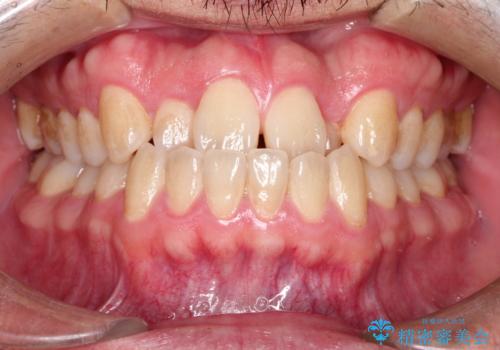

すきっ歯のワイヤー矯正による治療

- 前歯の隙間を閉じたいとのことで来院されました。

ワイヤー矯正にてスペースを閉じで、上下の歯のかみ合わせを改善することとなりました。

矯正治療には多少の痛みが伴いましたが、隙間もなくきれいな歯並びへと改善されました。